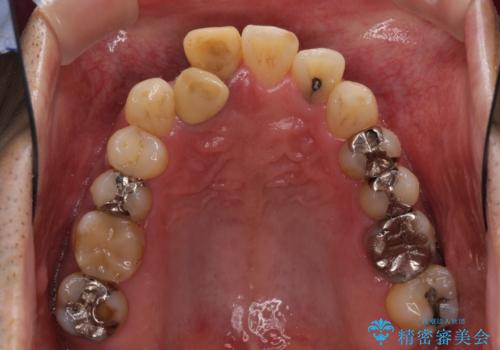

- 隠れるほどに内側に転位しいてる前歯を気にして来院された患者様です。

仕事柄海外出張が多いとのことで、インビザラインにて矯正治療を行うこととしました。

矯正治療後は、前歯や下顎の奥歯など、むし歯治療途中の歯をオールセラミッククラウンにて補綴治療を行うこととしました。